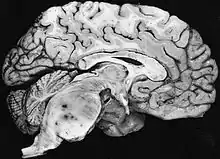

| Diffuse fibrillary astrocytomas arising in the brain stem favor the pons: The tumor here produces the classic hypertrophy of the affected region. | |